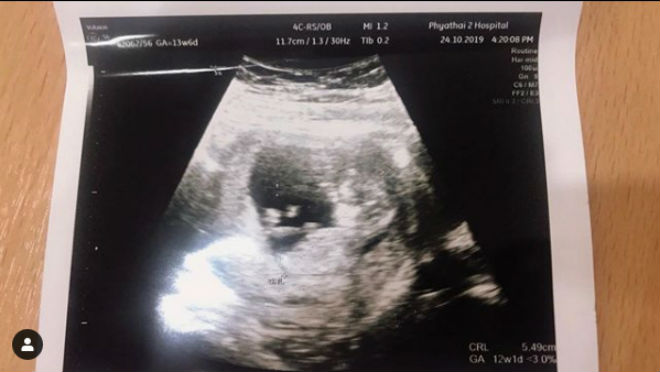

Trên trang cá nhân, Dangda vừa vui vẻ khoe ảnh phim chụp siêu âm hình ảnh bà xã của mình đang mang thai đứa con thứ 2 của họ. Nhiều cựu danh thủ và đồng đội hiện tại của tiền đạo 31 tuổi này ở ĐT Thái Lan như "Messi Thái" Chanathip Songkrasin, Theerathorn Bunmathan, Tanaboon Kesarat, hay Charyl Chappuis đã gửi lời chia vui với anh và gia đình trên mạng xã hội Instagram.

Dangda vui vẻ khoe ảnh vợ mình mang bầu đứa con thứ 2